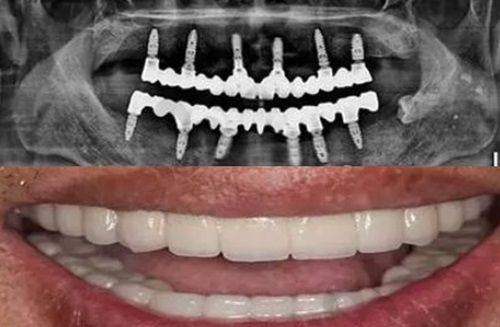

深圳同步齿科同富门诊(布吉店)拥有一系列精良的牙科诊疗设备,如CBCT机、全景机、超声洁治器、急救设备、根管测量仪、根管填充器、激光设备、电动吸引器、口腔内窥镜等。这些设备为正确诊断和有效治疗提供了有力的支持。

CBCT机可以提供三维的口腔影像,帮助医生更清晰地了解患者口腔内部的结构,对于种植牙等复杂手术的规划非常有帮助。全景机则能拍摄全口牙齿的影像,让医生全方面了解牙齿的整体情况。超声洁治器可以效率高地清除牙齿表面的牙结石和菌斑,起到口腔清洁和预防保健的作用。